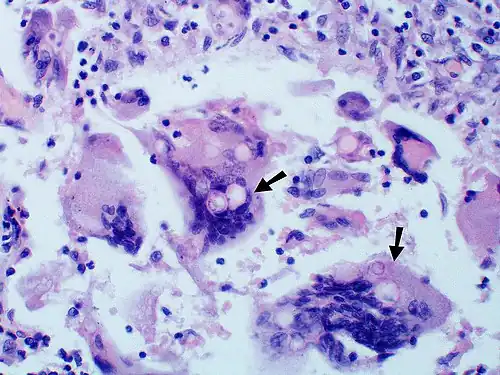

-

Large yeast-like fungi seen within giant cells at arrows. Budding yeasts in the cytoplasm of giant cells at the arrows. Broad-based budding and double-contoured cell walls are seen in the giant cell in the center are characteristic of Blastomyces dermatitidis.